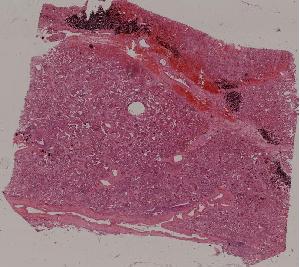

51. Carnification of the lung